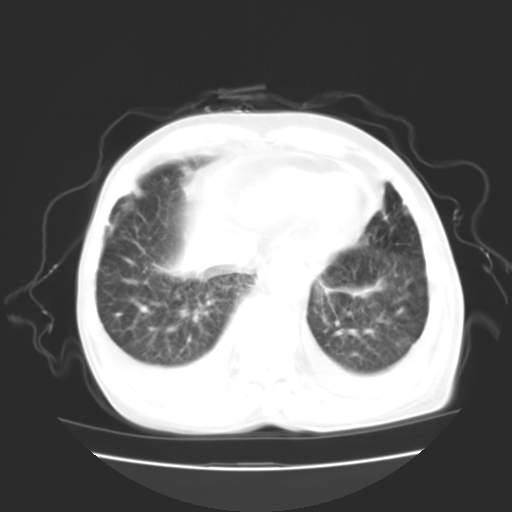

女70y乳腺ca(针吸活检)

多部位转移瘤的诊断可以肯定,我的疑问是:双肺对称高密度影及胸水是否为心衰肺水肿,病人体虚弱,不好意思图象传的乱![em9]

肺部病变为淋巴转移,肝脏转移,及局部淋巴转移。胸水可能为淋巴回流受阻(血性的考虑胸膜转移)

1)左侧乳腺癌并左侧腋窝及纵隔淋巴结转移,两肺淋巴道转移(癌性淋巴管炎),肝脏多发性转移。2)双侧胸腔积液。3)慢性胆囊炎。

3、双肺癌性淋巴管炎;

4、双侧胸腔积液(考虑淋巴回流障碍所致);

1)左侧乳腺癌并左侧腋窝及纵隔淋巴结转移,肝脏多发性转移。2)双侧胸腔积液伴双肺蝶翼样磨玻璃高密度影,双侧肺门血管影增粗(图像不全,肺门层面没纵隔窗),考虑心功能不全所致。3)慢性胆囊炎伴壁钙化。